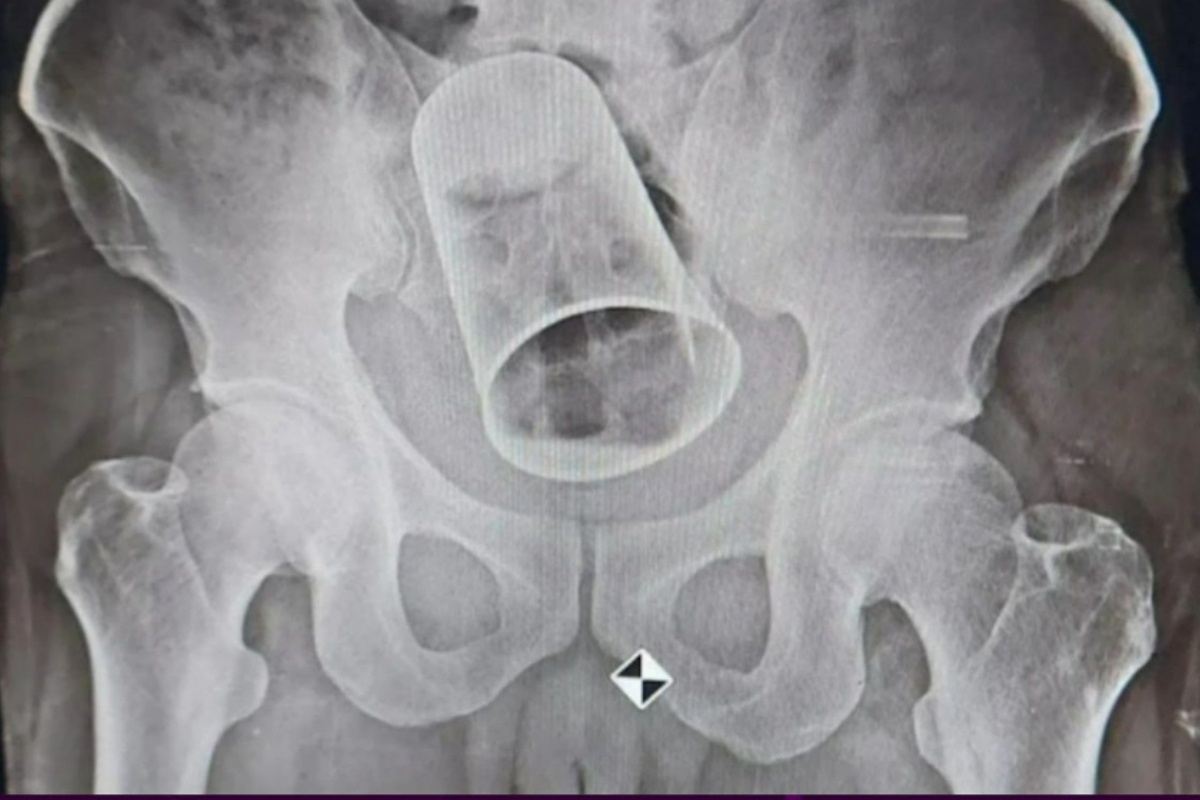

Steel glass surgically removed from a man’s rectum after 10 days

A strange and potentially dangerous act done in the name of “friendship” almost killed a man. During a party in Surat, Gujarat, a man’s friends are said to have put a steel glass in his rectum, which is the last few inches of the large intestine.

The man, Krushna Rout, was drunk when the incident happened. He is from Odisha. After 10 days, when he went back to Odisha, he had surgery to get the glass out.

The surgery was done at the MKCG Medical College and Hospital in Brahmapur. Online, a picture of his X-ray has been found.

His stomach started to get bigger because he couldn’t go to the bathroom. Rout went to MKCG Medical College and Hospital to get an x-ray, and the results shocked the doctors because they showed that a piece of glass was stuck in his rectum.